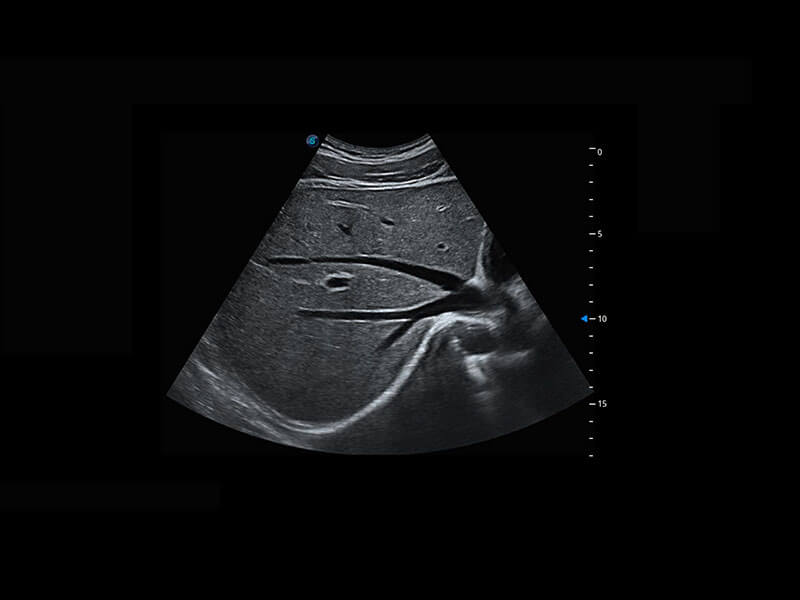

胎心筛查

P60搭载一系列胎儿心脏成像技术,实现精细的胎儿心脏评估。

• 四腔切面

• 四腔心血流

• 右室双出口

• 胎心容积成像